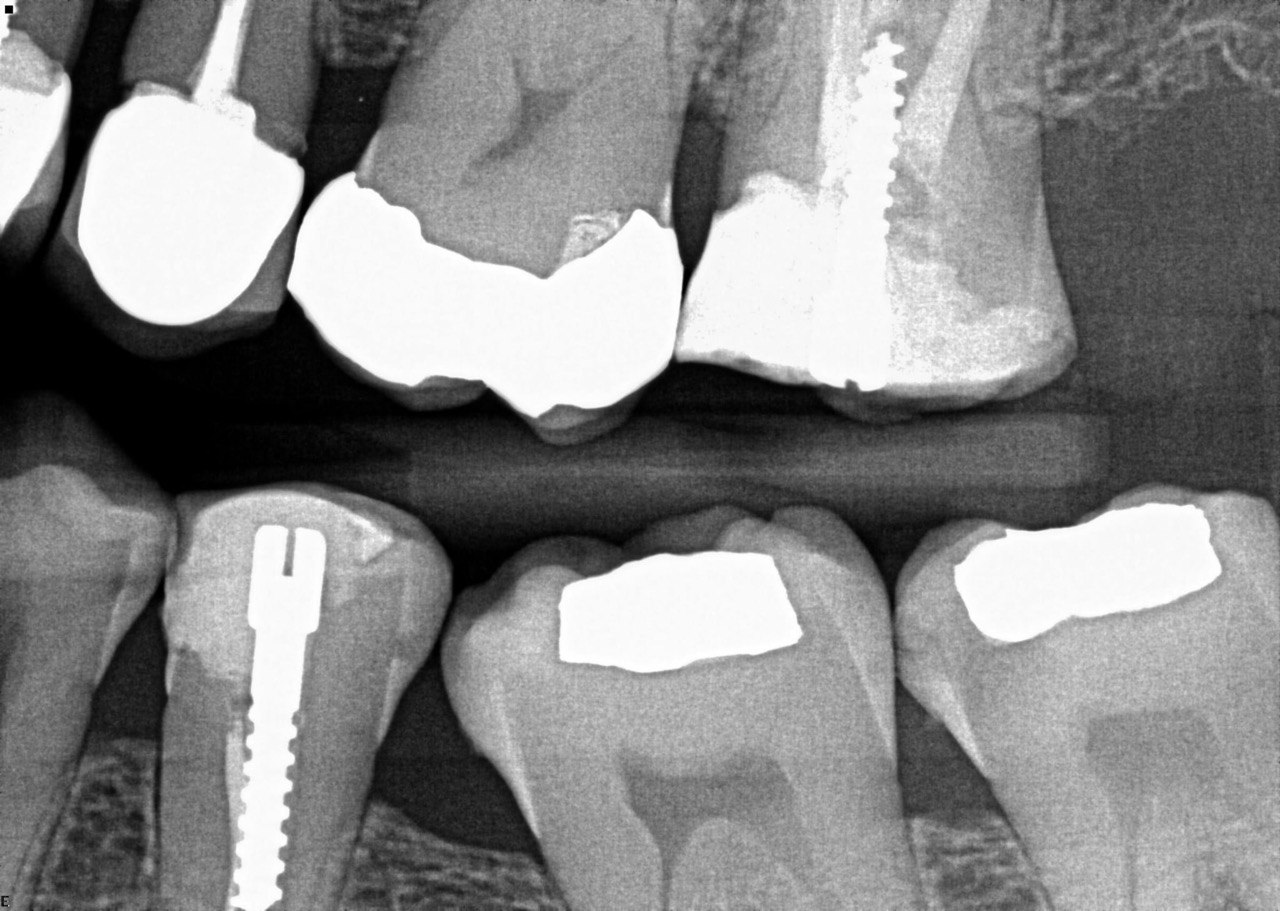

Quistion 11: What are the conditions of the distal and mesial surfaces of the tooth # 4.5 respectively?

Question 12: What option can describe the mesial surface of the tooth # 3.7?

Question 13: What option can describe the mesial surface of the tooth # 3.8?

Question 14: What option can describe the mesial surface of the tooth # 3.4?

Question 15: What option can be selected for treatment of the caries in mesial surface of the tooth # 3.4?

Question 16: What option can be chosen for the treatment of the mesial surface of the tooth # 3.7?

Question 17: What are the caries extention in distal of the tooth # 2.4 and mesial surface of the tooth # 2.5 respectively?

Question 18: What is the option that can describe the distal surface of the tooth # 1.7?

Question 19: What is the option that can describe the mesial surface of the tooth # 1.8?

Question 20: What is the option that can describe the distal surface of the tooth # 4.5?

Question 21: What options can describe the mesial and distal surfaces of the tooth # 4.7 respectively?

Question 22: What codition cannot be seen in the lower teeth in this X ray?

Question 23: What option can describe the distal surface of the tooth # 4.5?

Question 24: Which condition can be detected in the following X ray?

Question 25: What treatment is appropriate for distal surface of the tooth # 3.4 and mesial surface of the tooth # 3.5?